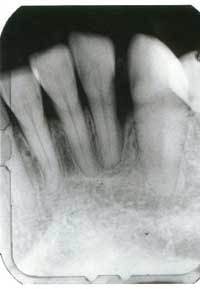

Patient usage has demonstrated dramatic improvements as is evident when comparing the initial probing results (Figure 2) with the after treatment results (Figure 3). The patient was a juvenile diabetic and suffered from periodontal disease for a number of years. The cost to the patient was substantially less than the cost of comparable conventional method and the results have been maintained.